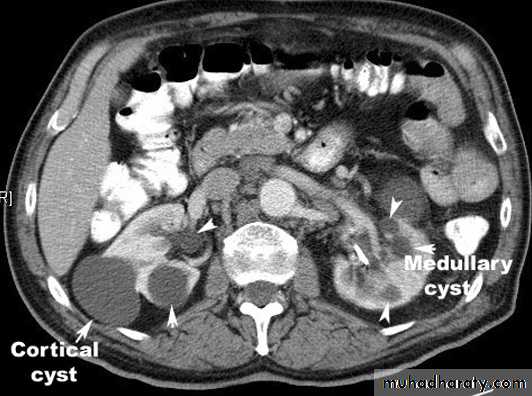

• Simple renal cysts• This represent the most common renal mass lesion.

• The incidence increasing with age and are present in

• 25-50% of subjects over the age of 50.

• These lesions are, by definition, simple with a thin

• wall and contain only serous fluid. They are found

• incidentally.

• On US: well demarcated, thin wall, homogenous fluid contents cyst with

• posterior acoustic enhancement.

• At CT: spherical mass with imperceptible wall, its contents are

• homogenous of fluid density (0 – 20 HU) with sharp margins